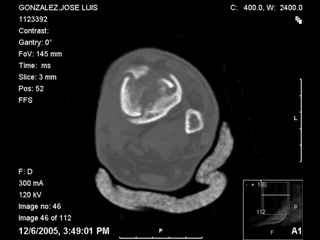

I have attached his x-rays. I have also attached an WMV movie file of his axial CT (if you are unable to view this, I can post an MPEG file).